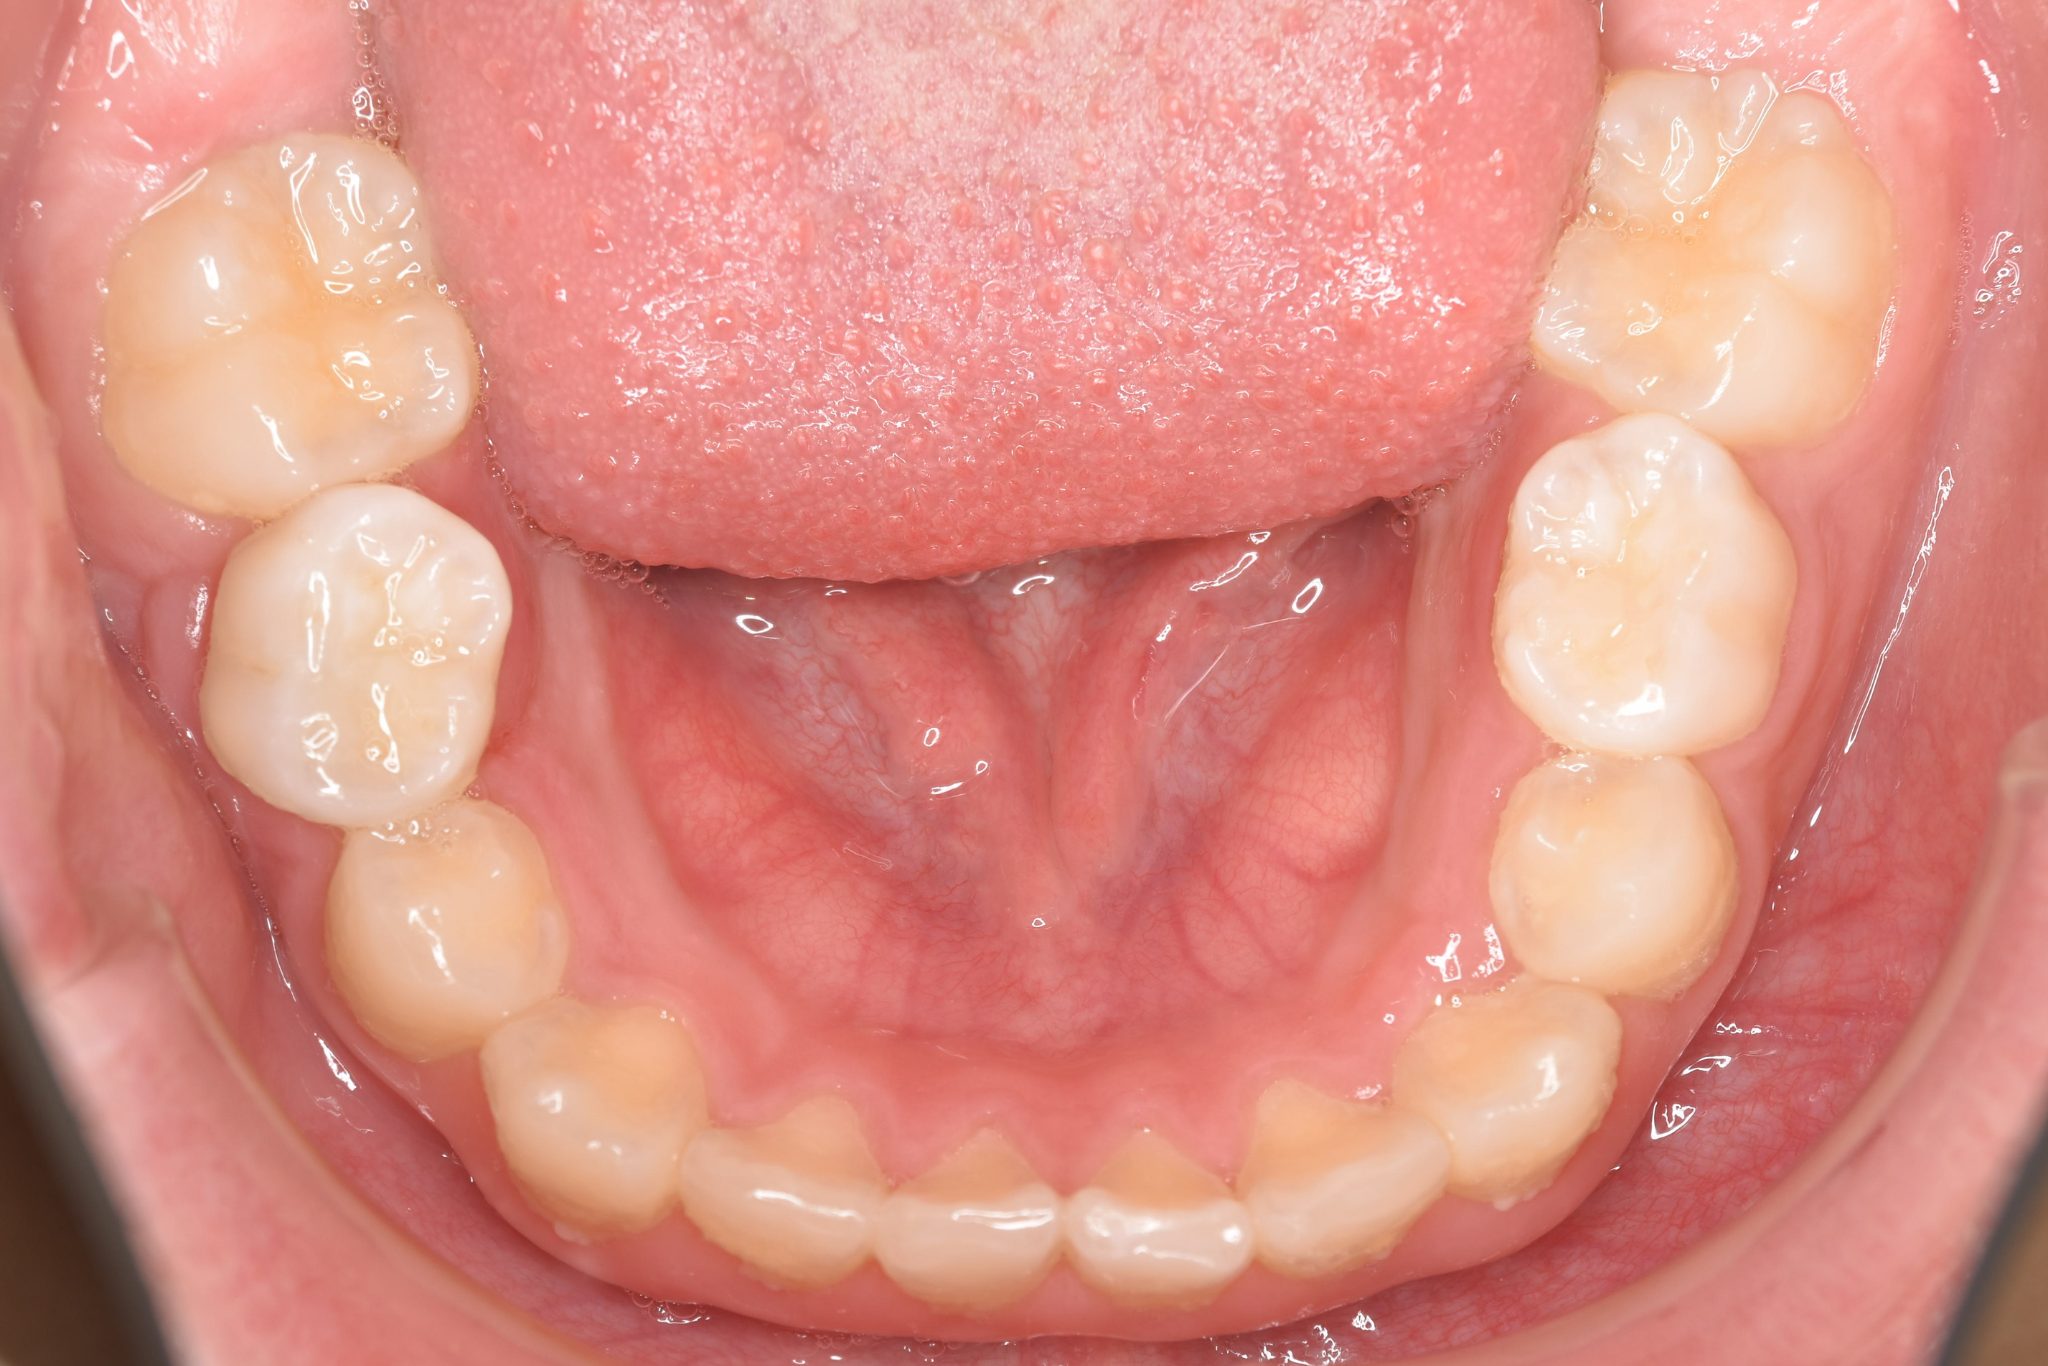

アフター

全顎ワイヤー矯正 症例_218